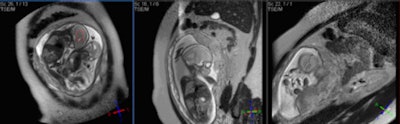

| Sagittal HASTE image used for planning further fetal images in other planes, taken at the Clinical Research Imaging Center, University of Edinburgh. Image courtesy of Janet De Wilde, PhD, and Dr. Scott Semple. |